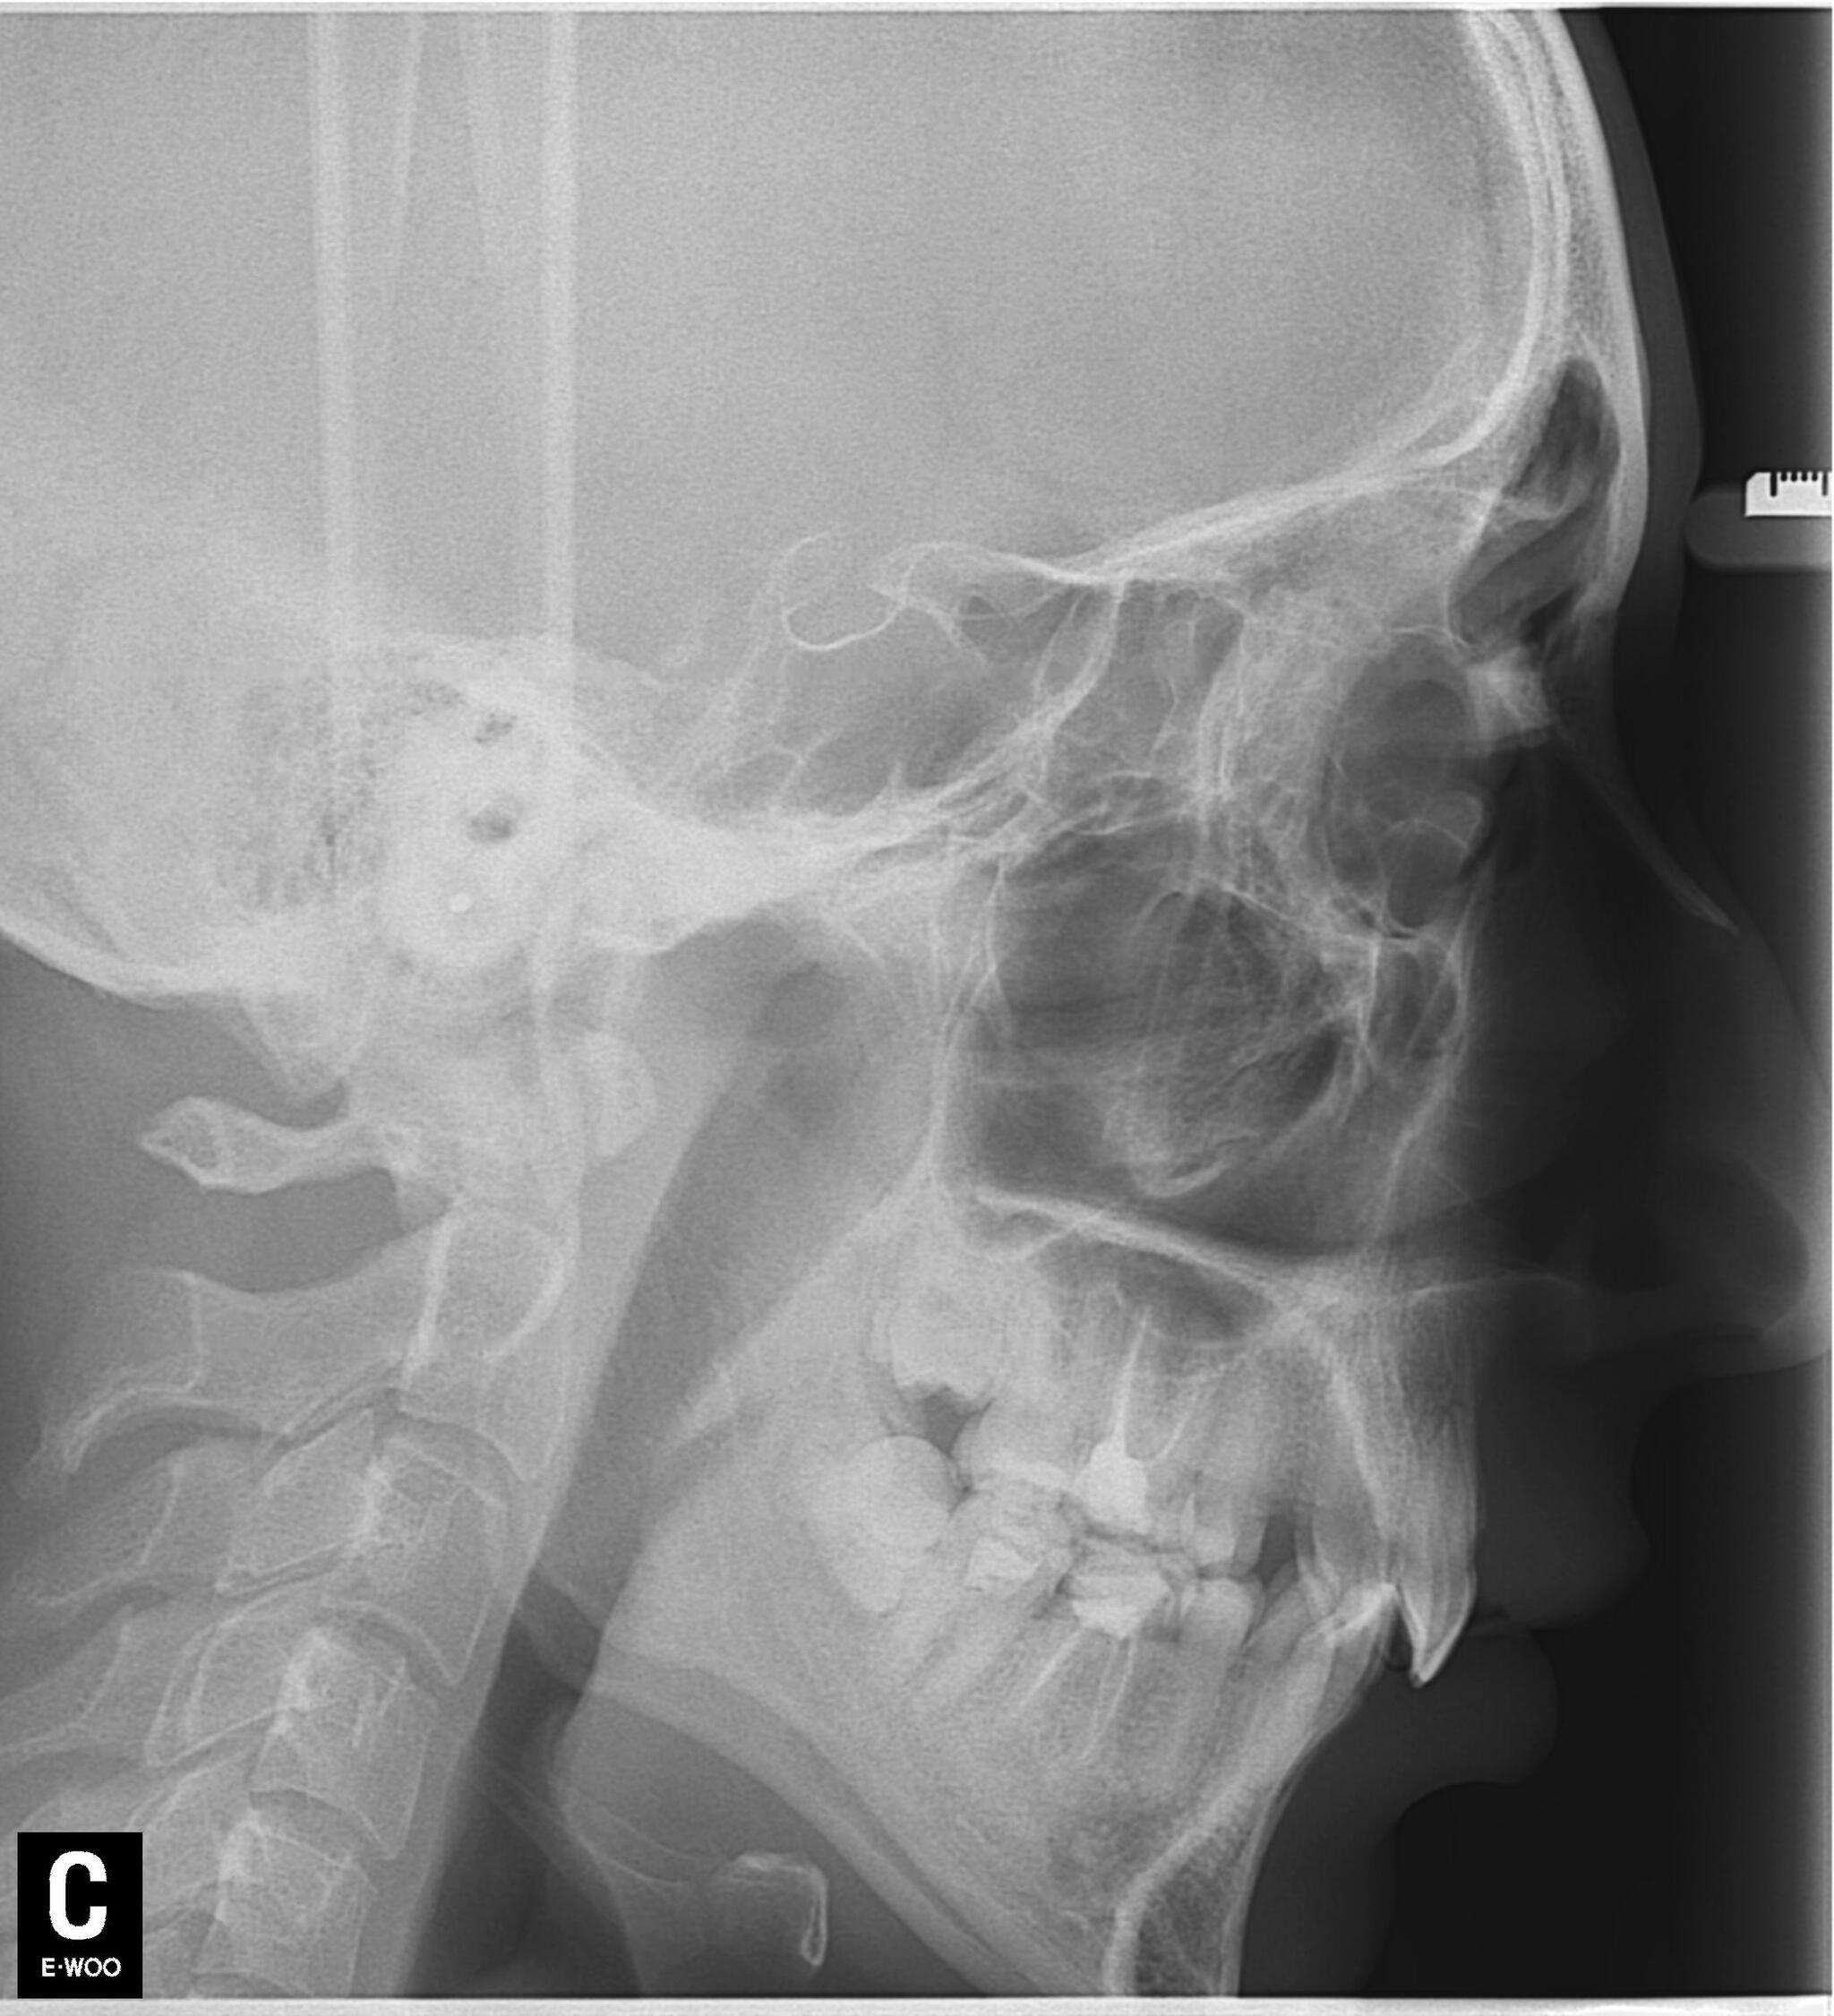

Как я выглядел(слабонервным не смотреть):